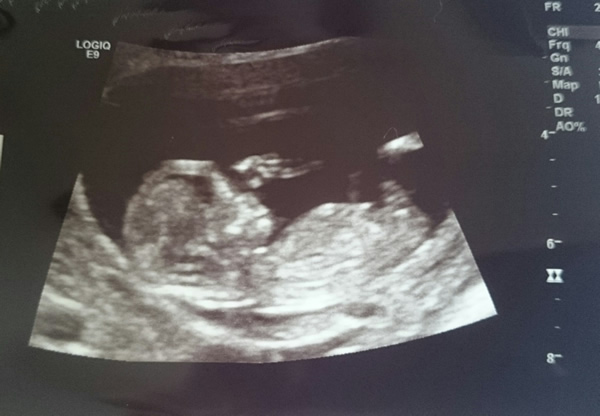

Hi, here are a few pics from my 12 week scan. I'm not sure if I can make out a nub but a few people think they can. Anyone have any guesses from nub and skull theories?? Thanks so much :)

Can't say I see a nub but I think I get a girly vibe from these...

The skull definitely looks quite different to my son's ultrasound pics. His head looked bigger and more angular. I hope that's a sign this could be a little girl. Trying not to get carried away though...

Maaaybe girl but not great pics and 12w is still early.

12 weeks is so early still. I'm going to guess boy.

Girly skull, but I can't see a nub. FX!